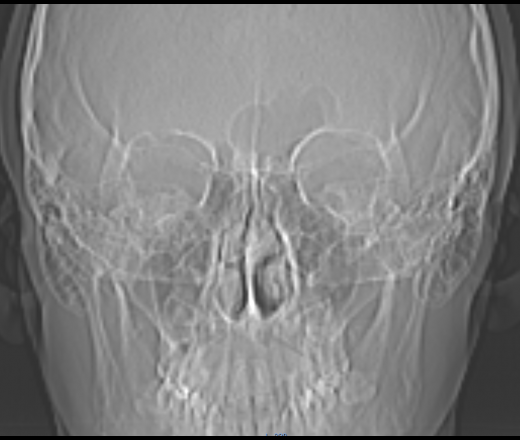

Острый верхнечелюстной синусит, КТ после ~1 месяца лечения(курс антибиотиков + сосудосуживающие(неделя), а также топические интраназальные стероиды + промывания солевым раствором + муколититики (всё время лечения)).

Нужен совет по дальнейшей тактике лечения (остались выделения из носа)